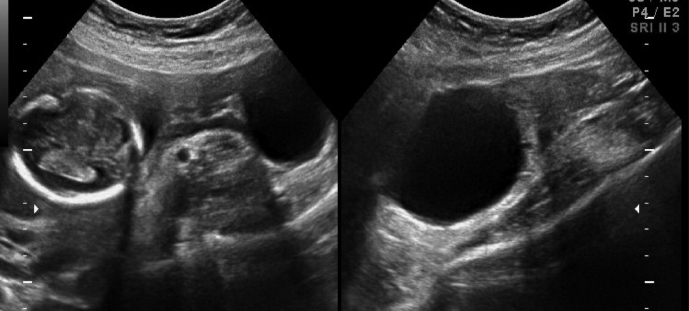

Management of Undesired Pregnancy of Unknown Location and Early Abortion